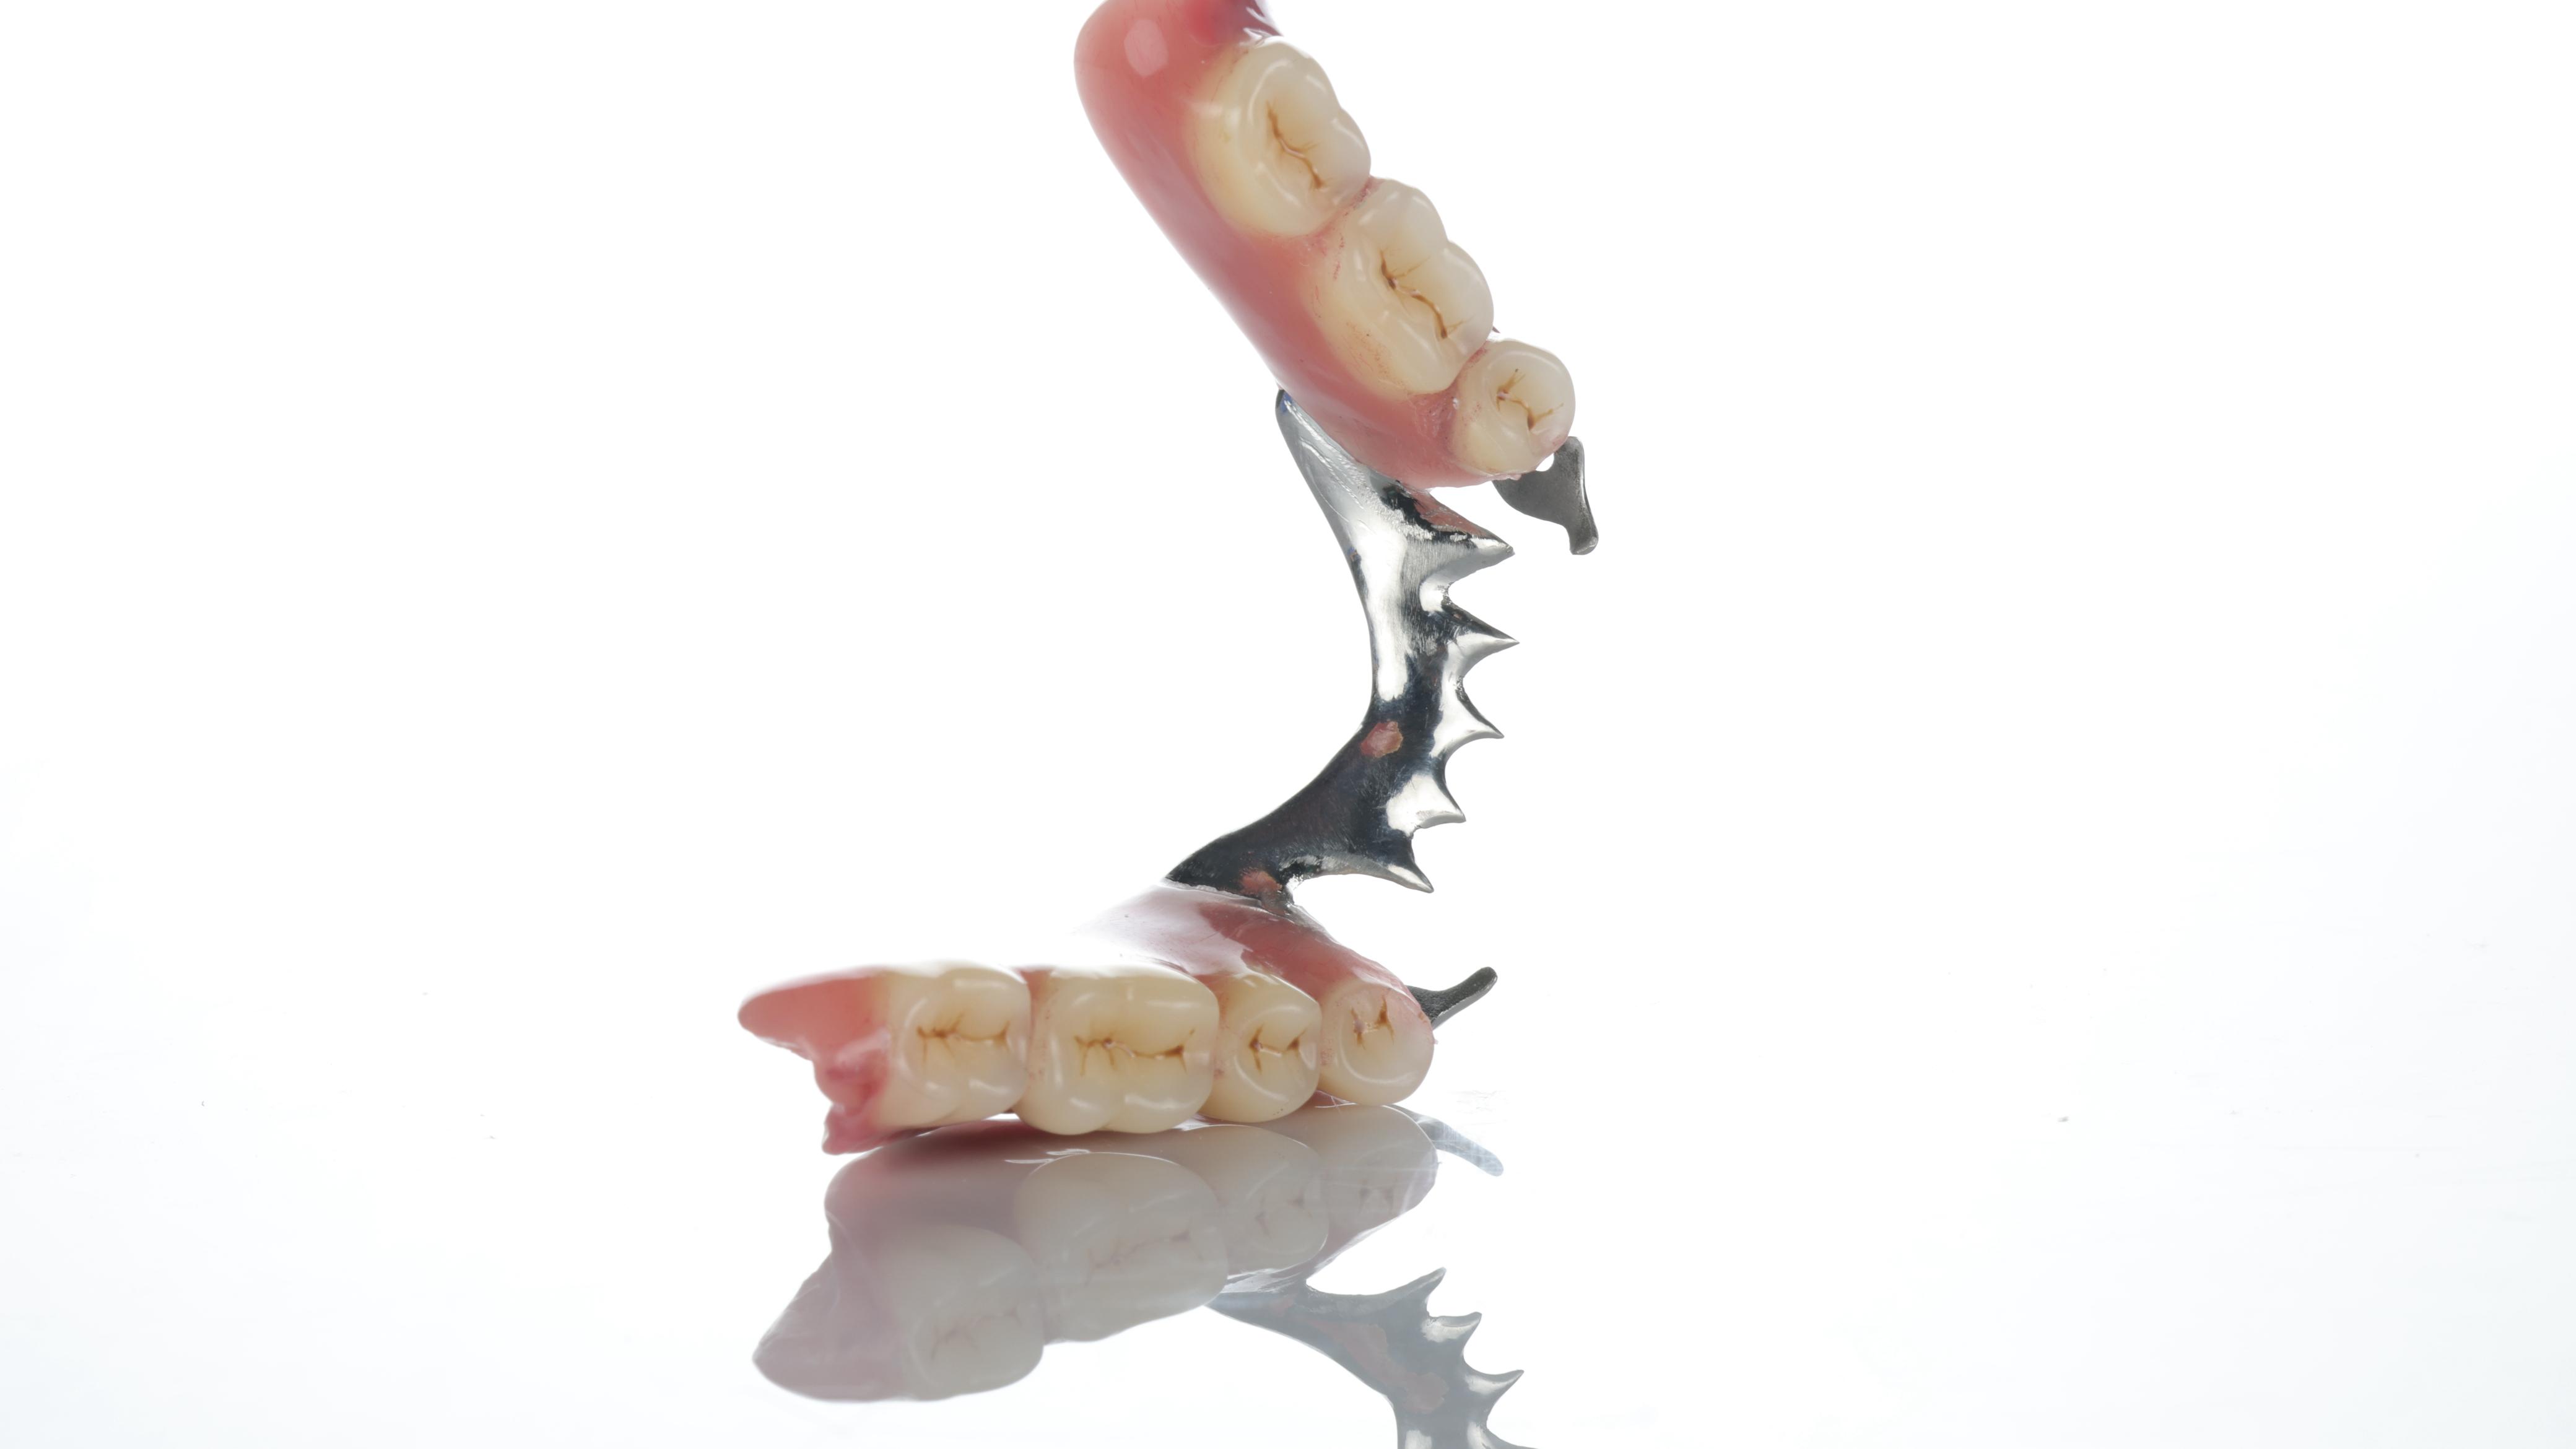

Cases